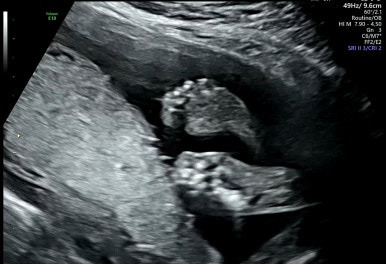

28주 1일

입체초음파로 태아의 얼굴을 볼 수 있는 시기이다!

제일 기다렸던 때이고, 다행히 태아 얼굴을 볼 수 있었다.